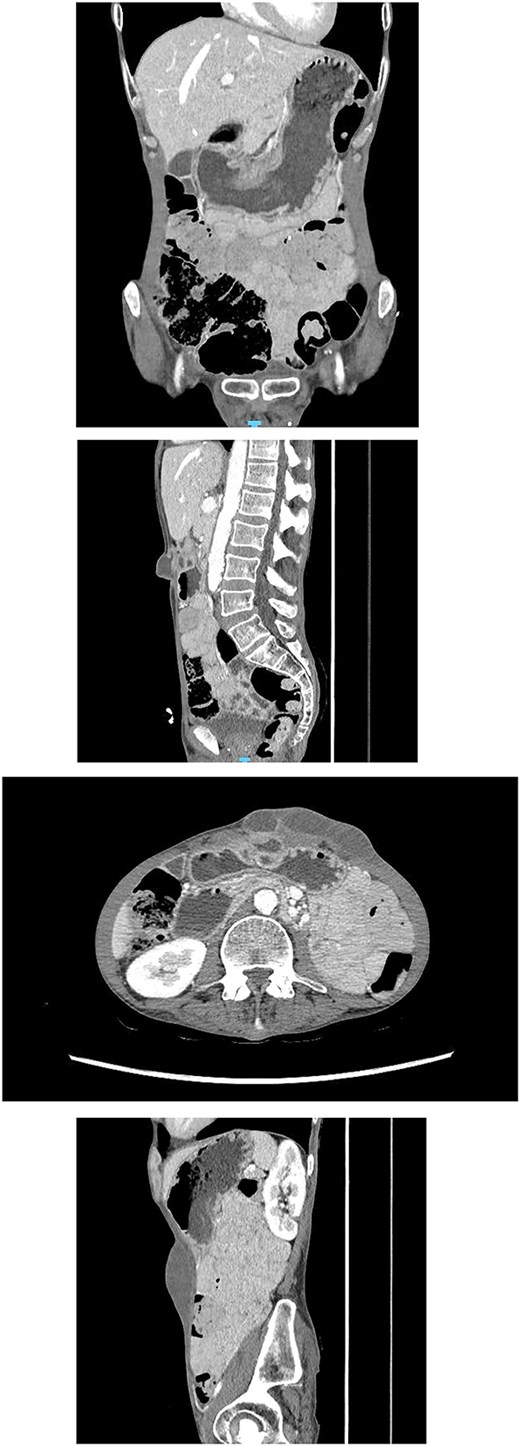

CT abdomen (Fig. 3): A multiloculated fluid collection at the superior greater omentum (7 × 3 × 4.6 cm) inseparable from the gastric antrum, extending into the anterior abdominal wall with a subcutaneous collection (9 × 3.5 × 2.8 cm). No free air or fluid.

CT abdomen showing a multiloculated fluid collection at the superior greater omentum (7 × 3 × 4.6 cm) inseparable from the gastric antrum, extending into the anterior abdominal wall with a subcutaneous collection (9 × 3.5 × 2.8 cm). No free air or fluid.